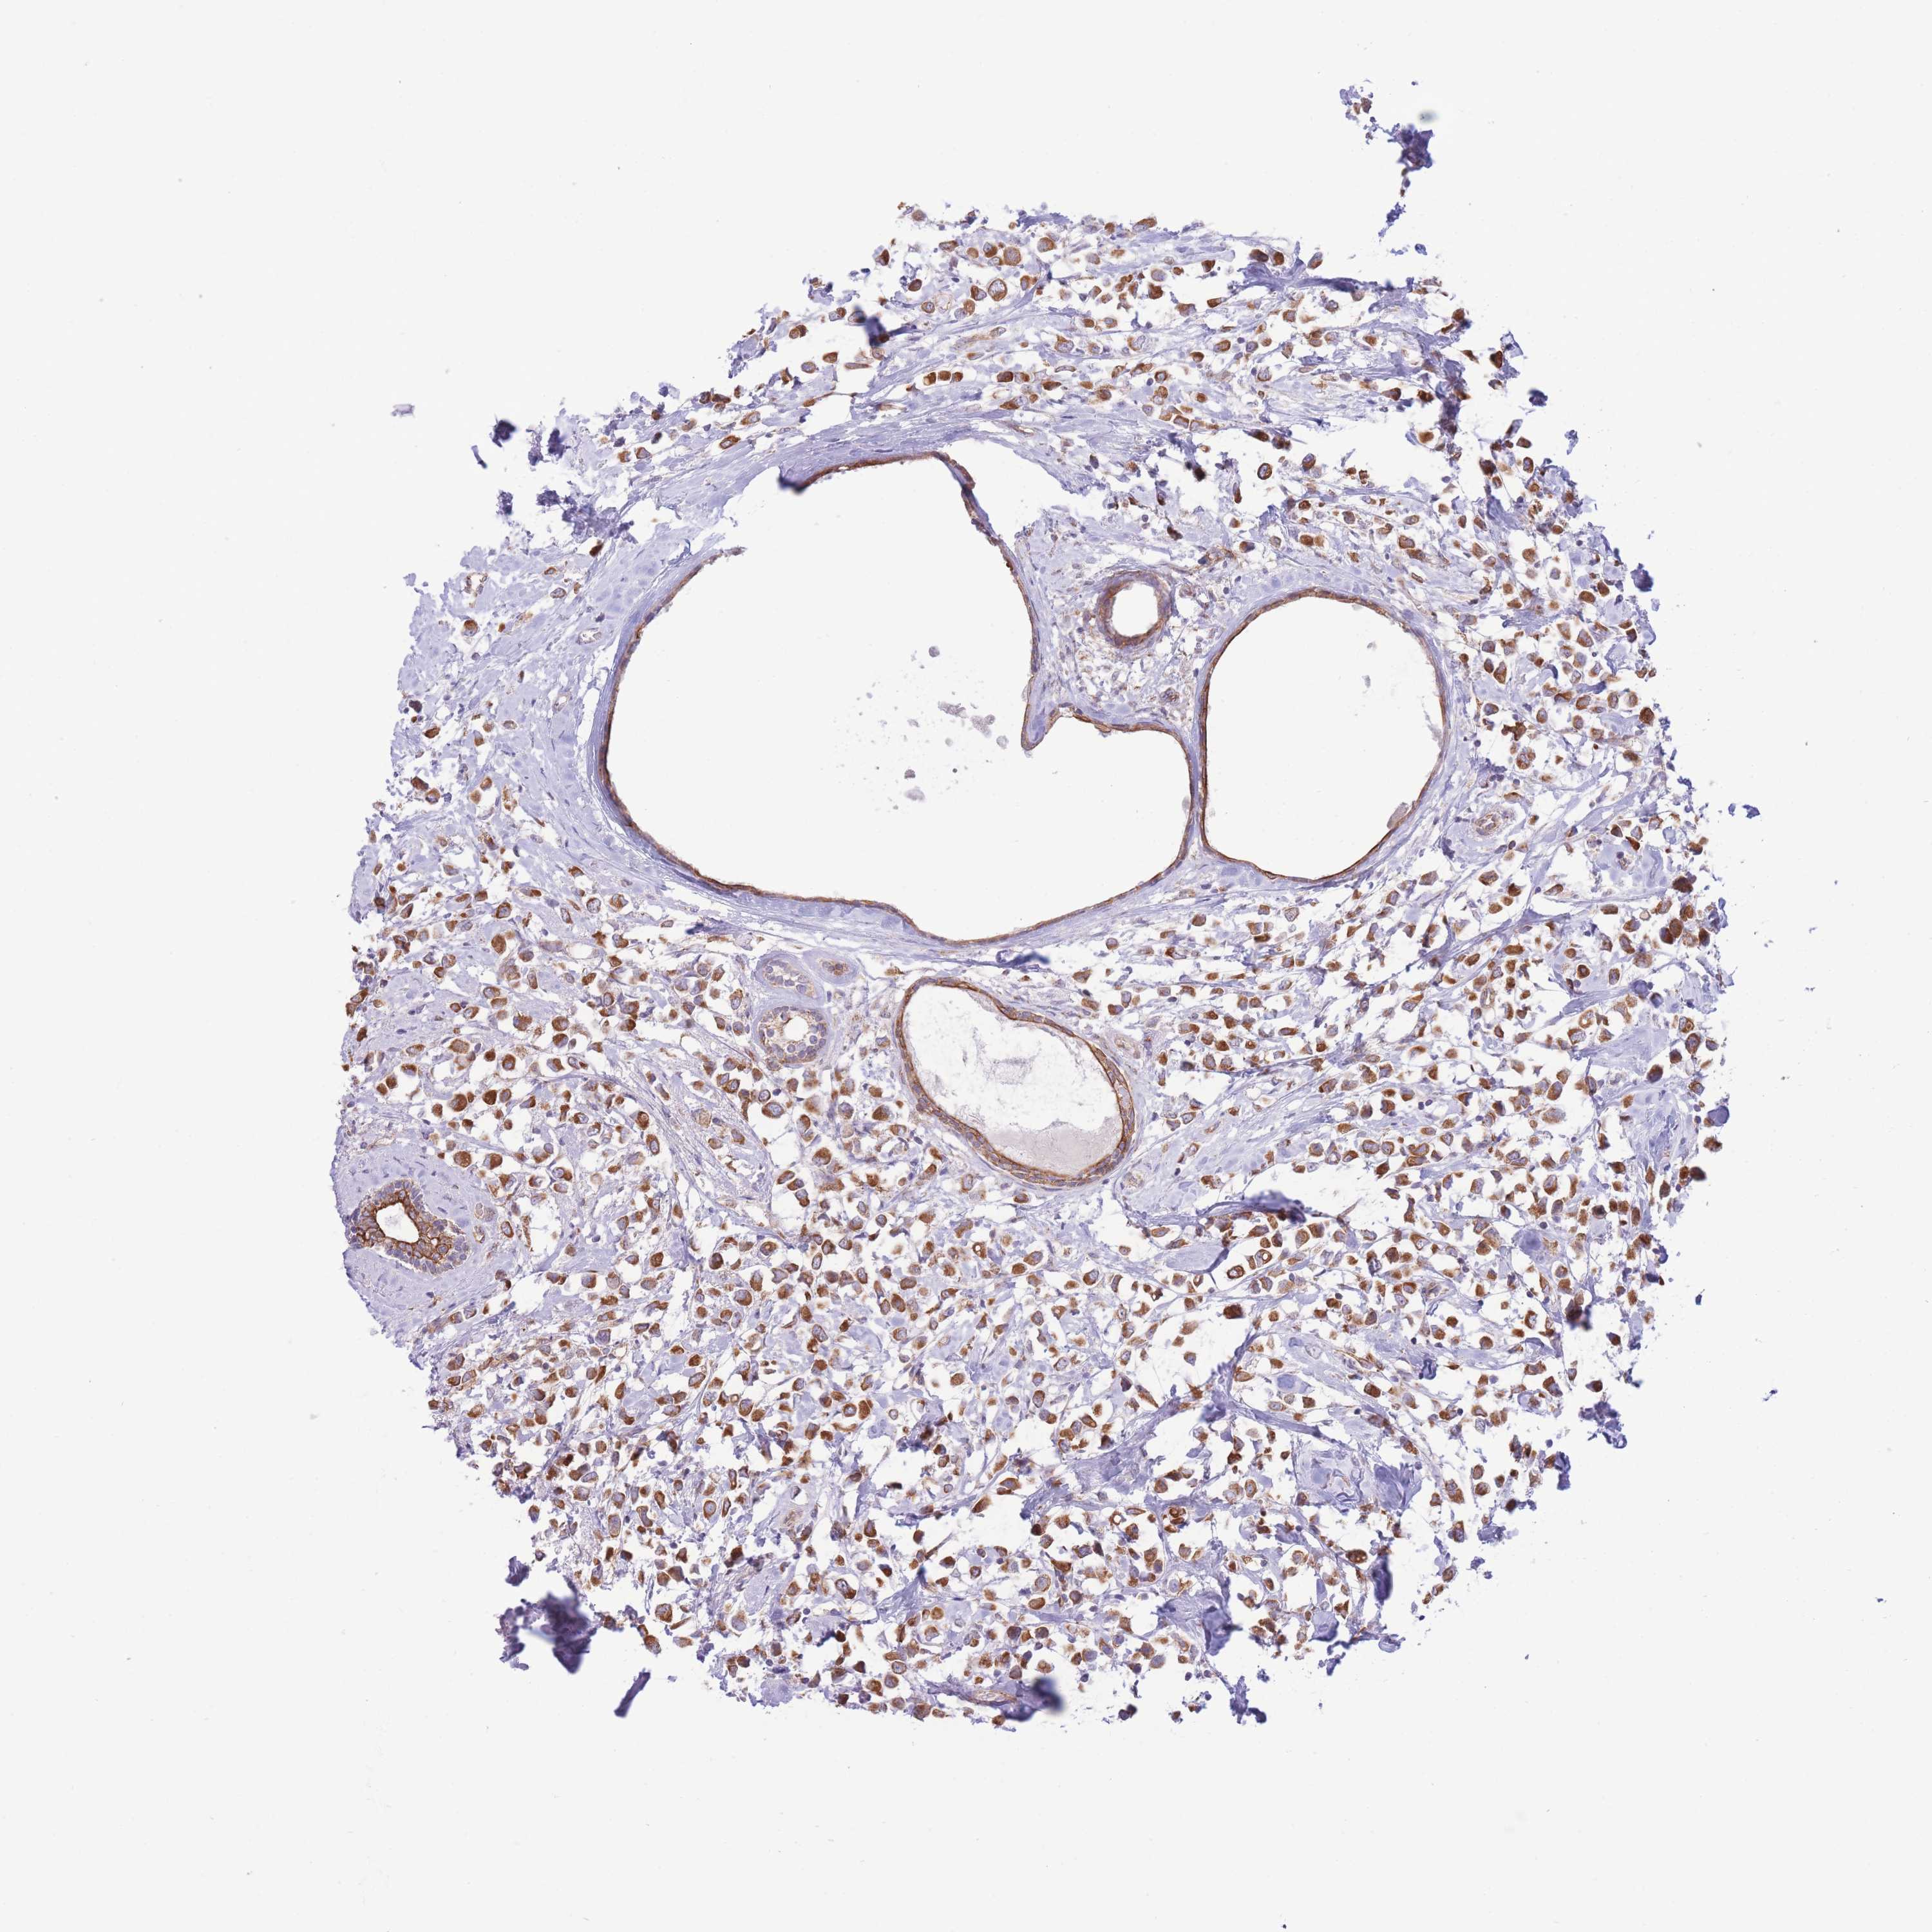

CANCER BREAST CANCER Show tissue menu

BRCA TCGA BRCA VALIDATION PROTEIN EXPRESSION

ANTIBODIES

AND

VALIDATION